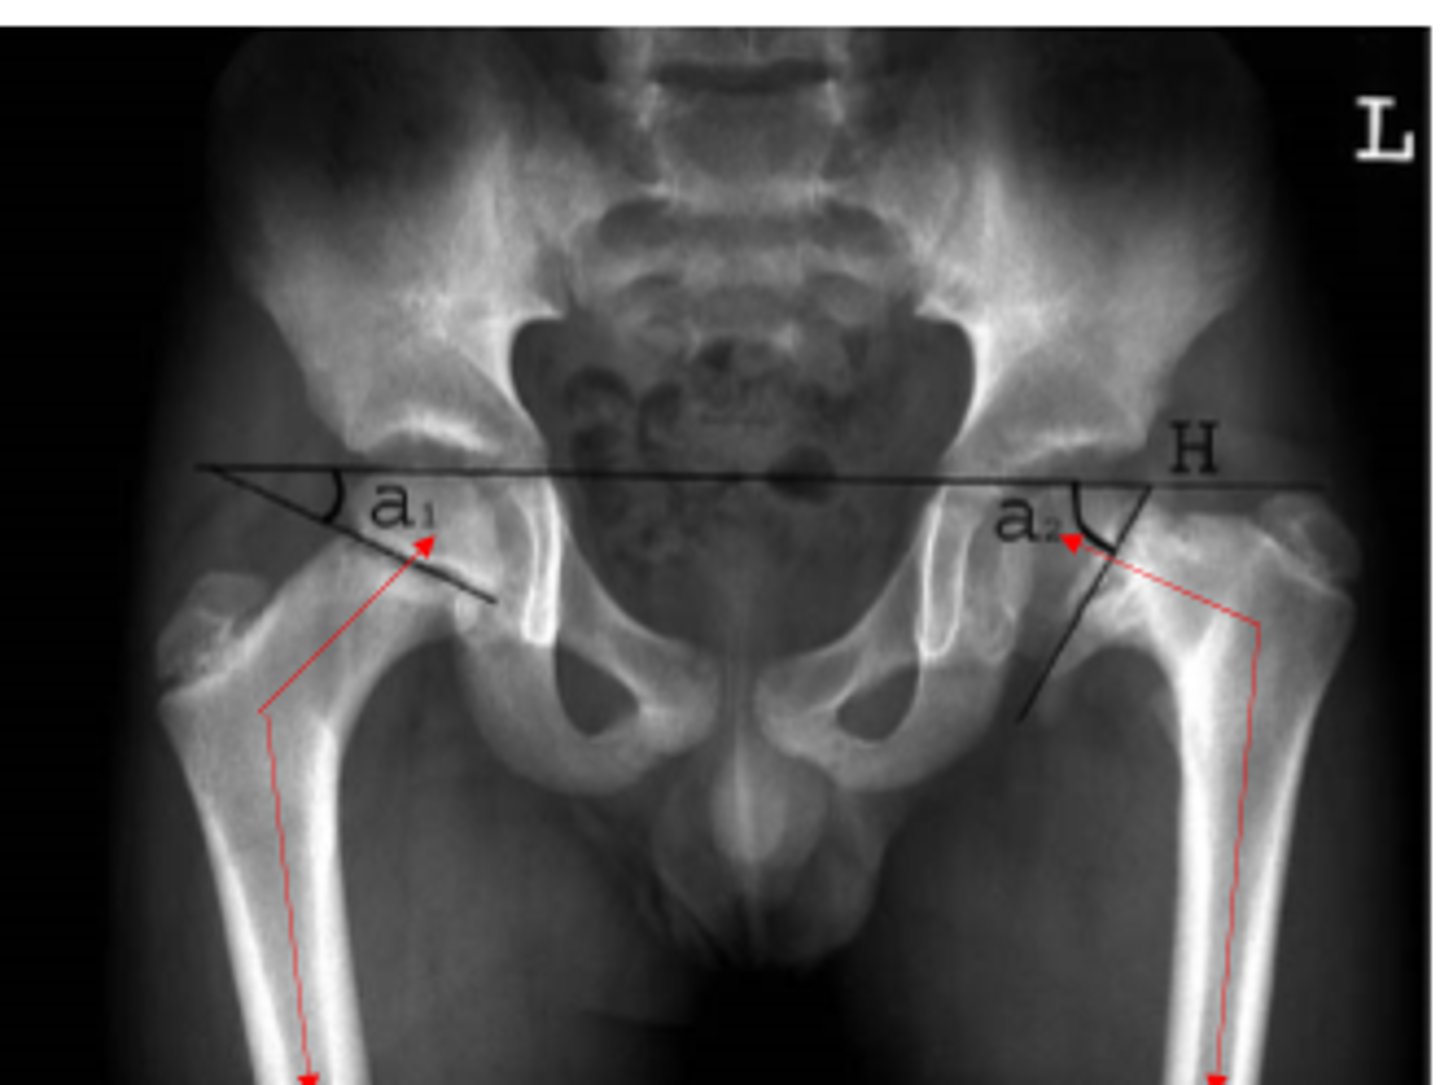

coxa valga

development of femur with angle of inclination GREATER than expected

*involves femoral head/neck and shaft

coxa vara

development of femur with angle of inclination LESSER than expected

varum, supinate

valgum, pronate

In an individual with a coxa vara hip, they may experience genu ____________ and therefore _____________ the foot.